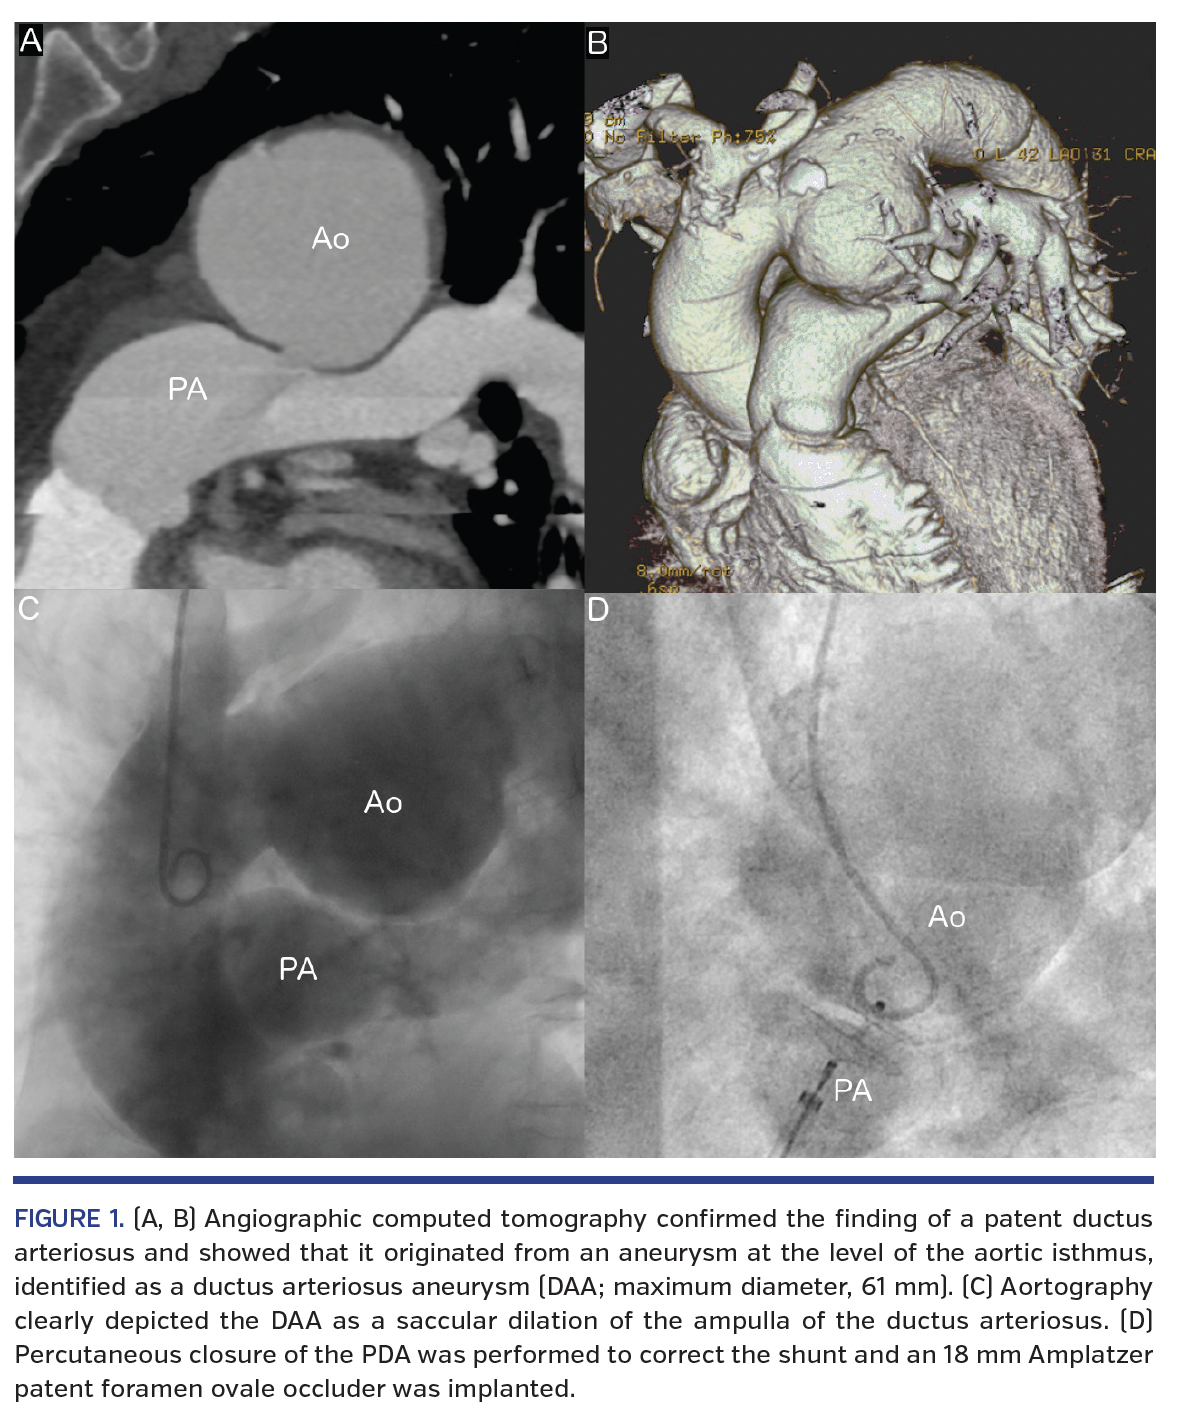

A 76-year-old hypertensive woman was hospitalized for recurrent dyspnea at rest and pedal edema, in a setting of heart failure with preserved ejection fraction. Her medical history included endovascular treatment for an aneurysm of the abdominal aorta and a recent hospital admission for bilateral pleural effusion. During the present hospitalization, a patent ductus arteriosus (PDA) was suspected at echocardiography. Angiographic computed tomography confirmed the finding of a PDA (Figure 1A) and showed that it originated from an aneurysm at the level of the aortic isthmus, identified as a ductus arteriosus aneurysm (DAA; maximum diameter, 61 mm) (Figures 1A, 1B).

Cardiac catheterization was performed. Aortography clearly depicted the DAA as a saccular dilation of the ampulla of the ductus arteriosus (Figure 1C). Significant left-right shunt through the PDA (Qp/Qs, 3.4) and postcapillary moderate pulmonary hypertension were measured.

Surgical correction of the DAA was excluded due to the high risk of the intervention and the frailty of the patient. Percutaneous closure of the PDA was performed to correct the shunt and an 18 mm Amplatzer patent foramen ovale occluder was implanted (Figure 1D). The choice of the device, with its double-anchoring disk, was dictated by the elevated pulmonary pressure, which was feared to possibly displace a conventional PDA occluder.